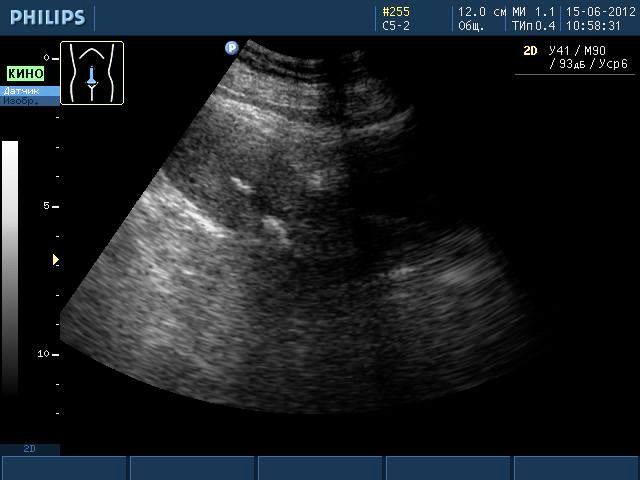

Эти образования хорошо визуализируются при проведении ультразвукового исследования или магнитно-резонансной томографии. Однако во время УЗИ невозможно увидеть ткани, из которых состоит образование, поэтому можно лишь предполагать наличие кальцината. Такая ситуация требует дополнительного обследования женщины, чтобы исключить более серьезные заболевания, чем просто наличие отложений солей кальция.

Одним из наиболее распространенных методов диагностики является ультразвуковое исследование репродуктивных органов. Гинекологи часто рекомендуют трансабдоминальное УЗИ, которое позволяет выявлять патологии органов с помощью датчиков, перемещаемых по животу пациентки.

- трансвагинальное УЗИ, которое обеспечивает более детальное исследование органа, особенно в период беременности;

- трехмерное УЗИ – современный метод диагностики заболеваний матки, который позволяет визуализировать кальцинаты в трехмерном формате;

На сегодняшний день трехмерное УЗИ считается самым точным методом диагностики заболеваний матки, однако его стоимость значительно выше по сравнению с другими методами.